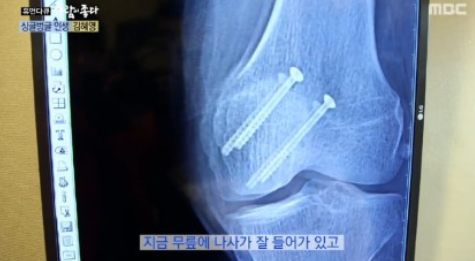

또 한 번은 지하 주차장에서 슬리퍼를 신고 넘어지면서 무릎뼈가 깨지면서 걷지 못할 정도의 상태였다고 하는데요. 뼈에 나사를 박는 등 2차 수술까지 진행해야 할 상황이었다고 하는데요. 그런 상황에서도 라디오 진행을 했다고 하는군요.